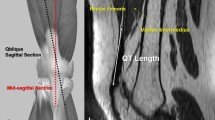

Two board-certified, pediatric musculoskeletal radiologists who were blinded to patient information, the operative report, and each other’s measurements, independently reviewed each 2D pre-operative MRI. The raters identified the sagittal image that showed the thickest portion of the quadriceps tendon and measured the anterior–posterior width of the quadriceps tendon at 10-mm increments, up to 40 mm as able based on the field-of-view, superior to the central aspect proximal pole of the patella (Fig. 1), as demonstrated previously by Zakko et al. Because the quadriceps autograft differs in diameter at the soft-tissue end (which becomes the tibial end of the neoligament) and the bone-end (which becomes the femoral end of the neoligament), the average measure at 10 mm superior to the patella was used to predict the bone-end diameter, and the average most proximal available measure was used to predict the soft-tissue end.

The correlation between the bone-end graft diameter and the MRI AP measure (mm) of the quadriceps at 10 mm above patella was weak and non-significant (Fig. 2; rs = − 0.03; p = 0.76). The MRI diameter significantly underestimated bone-end graft diameter (7.3 ± 1.1 mm vs. 10.6 ± 0.3 mm; p < 0.001). The correlation between the soft-tissue side graft diameter and the MRI-predicted graft diameter at the most proximal available measurement above the patella was strong and significant (Fig. 3; rs = 0.51; p < 0.001). As with the bone-end, however, the MRI measurement significantly underestimated the harvested soft-tissue graft diameter (7.4 ± 1.1 vs. 9.6 ± 0.8; p < 0.001).